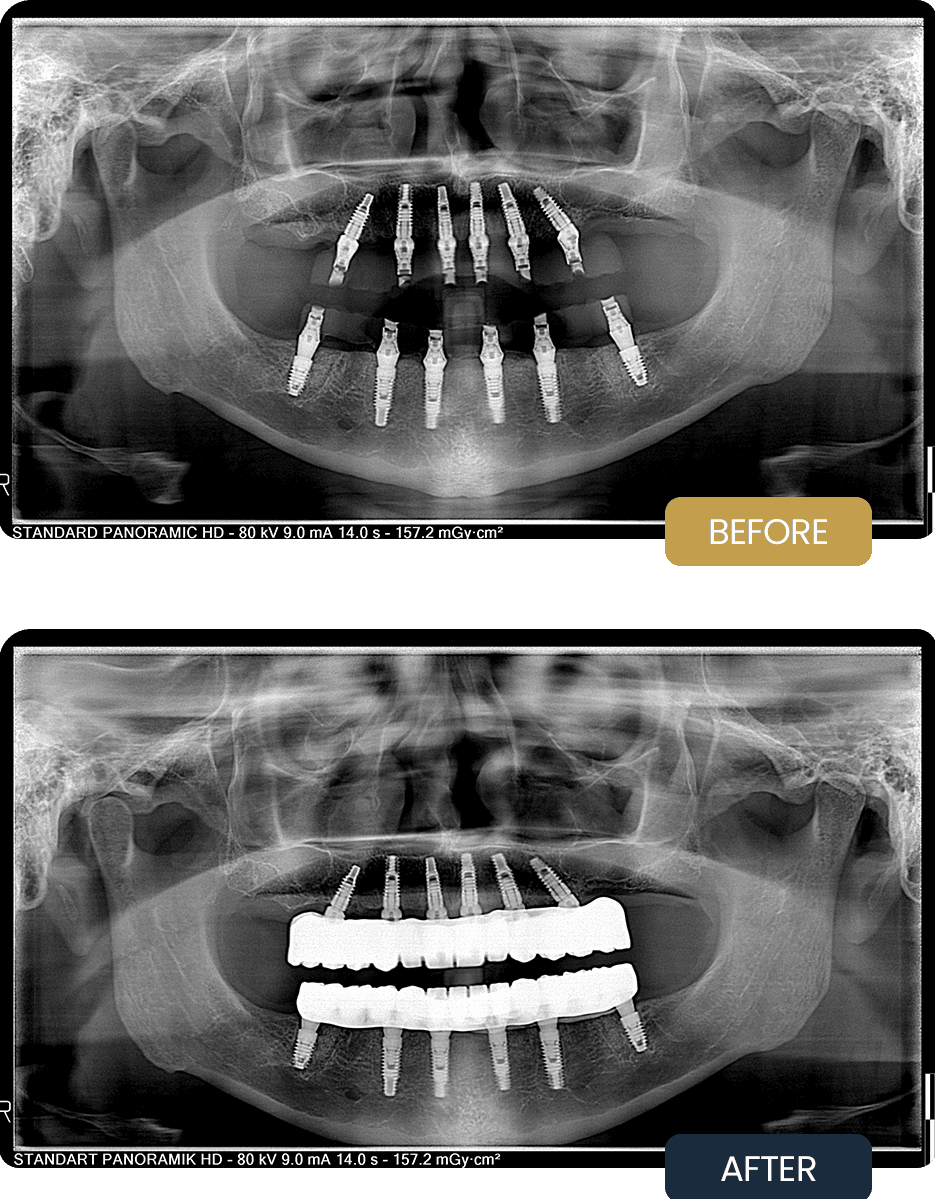

The pre treatment panoramic radiograph demonstrates the extent of tooth loss and the need for a complete implant supported rehabilitation to restore function and long term oral stability.

Post treatment panoramic imaging confirmed successful integration of all implants in both arches, with well positioned All on 6 supported restorations. The implants demonstrated stable placement, and the final prostheses provided balanced occlusion and strong structural support.